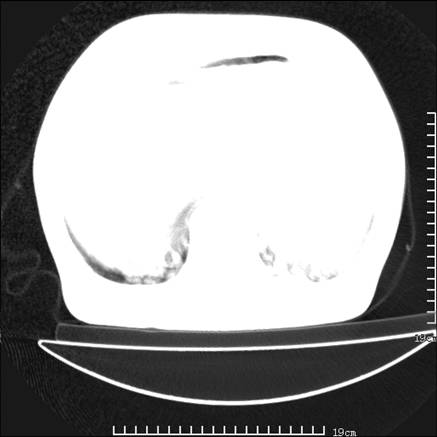

张男,75岁,干咳半年余,小便不利二年,b超检查前列腺增大,未见明显肿块;前列腺癌血生化检查多项指标明显增高。

双肺内多发转移瘤,纵膈淋巴结转移。来源前列腺?建议盆腔mri进一步检查。

双肺转移满了。

两肺广泛转移瘤。